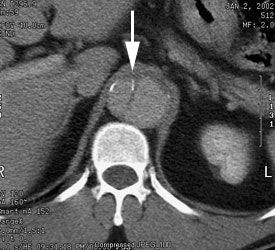

Eccentric calcifications along the dissection flap: Calcifications along the dissection flap are usually located along the true lumen side of the flap (white arrow). In this case the true lumen is to the right and the false lumen to the left. |